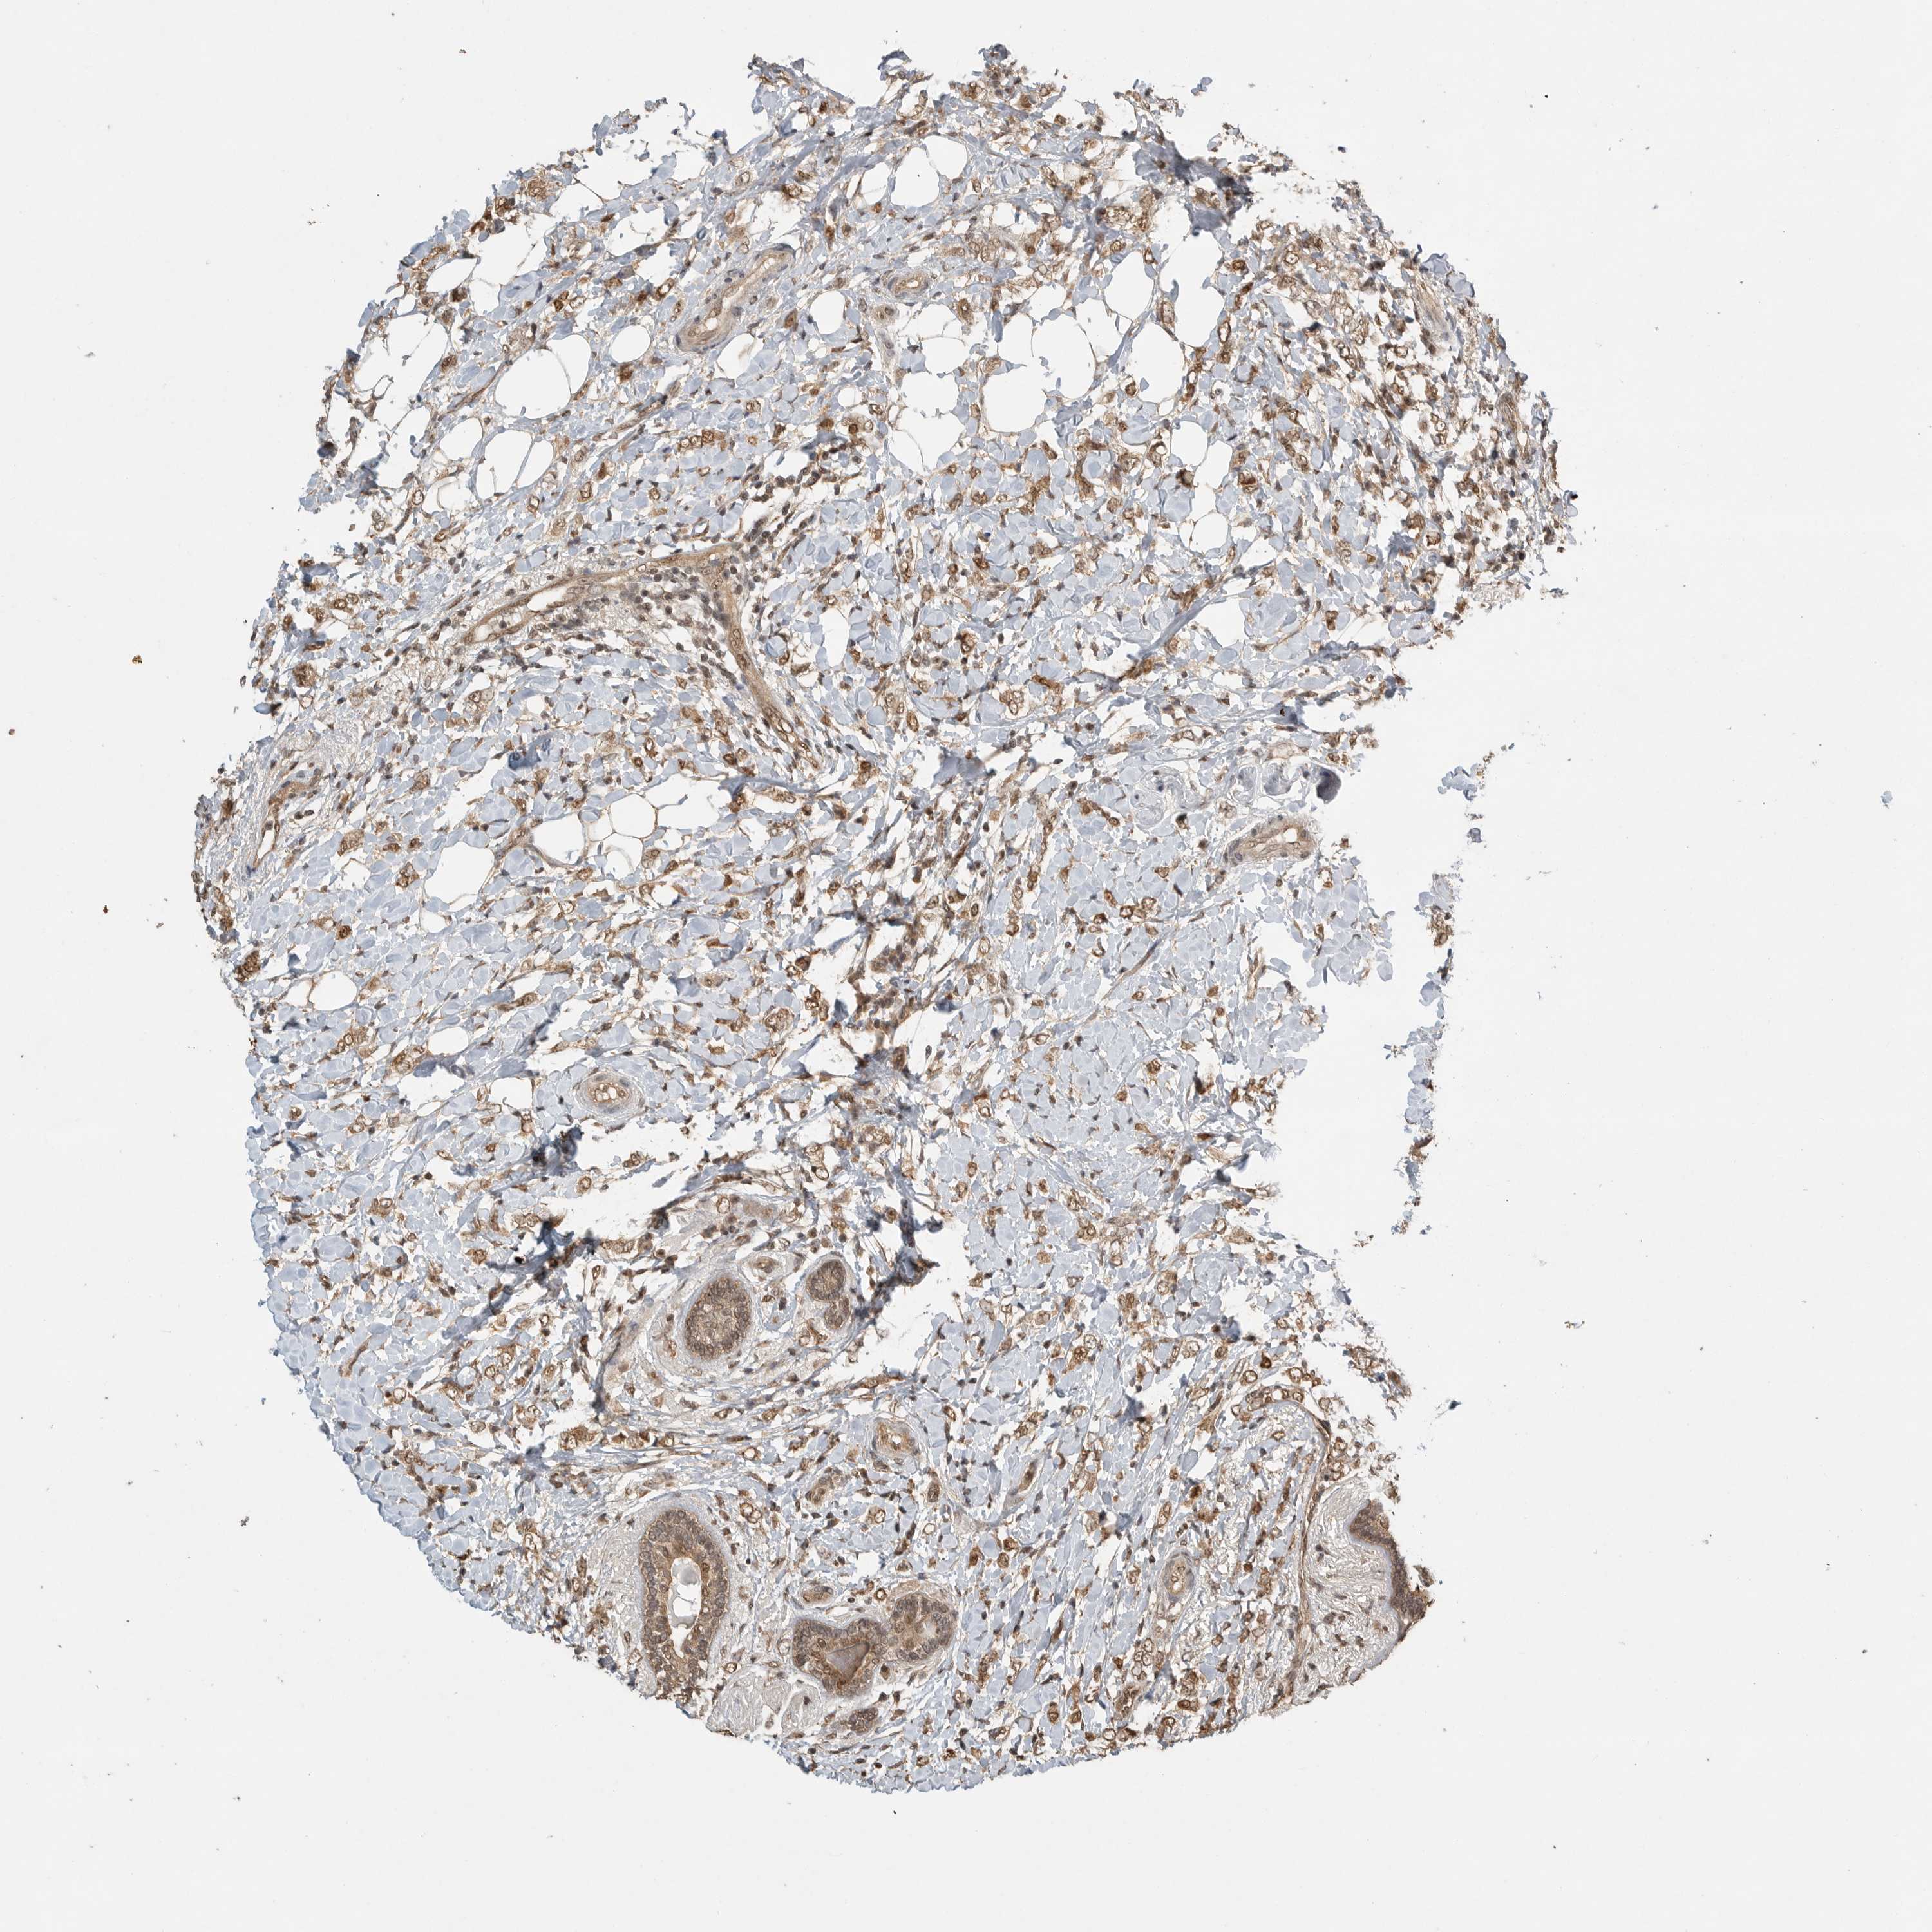

CANCER BREAST CANCER Show tissue menu

BRCA TCGA BRCA VALIDATION PROTEIN EXPRESSION